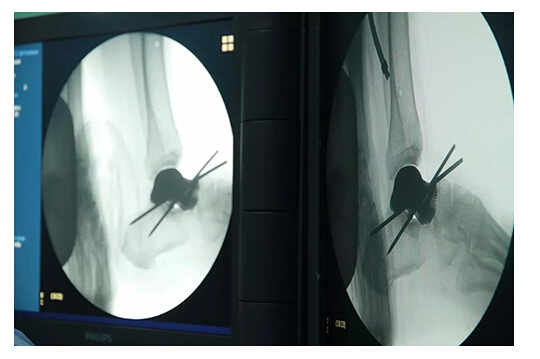

科室專家經(jīng)過反復(fù)多次討論和論證,解決了假體植入的手術(shù)路徑、手術(shù)器械、假體植入后的穩(wěn)定以及使用壽命和出現(xiàn)各種不良后果和并發(fā)癥的緊急預(yù)案,保證手術(shù)萬無一。

此次手術(shù)植入的3D打印全距骨假體是西安高新醫(yī)院骨一科醫(yī)療團(tuán)隊(duì)根據(jù)患者的病情,利用患者自身踝關(guān)節(jié)CT數(shù)據(jù)建立患側(cè)與健側(cè)的三維數(shù)字模型,根據(jù)健側(cè)距骨數(shù)據(jù)鏡像出患側(cè)距骨三維模型。為患者“私人定制”量身定做距骨與人體完全匹配,完全個(gè)性化制作。材料使用彈性、硬度和柔韌性與人體相似的鈦合金材料,假體關(guān)節(jié)面以外采取粗糙面有很多微孔有利于骨長入、肌腱韌帶附著,維持了踝關(guān)節(jié)的穩(wěn)定。具有良好的應(yīng)用前景。